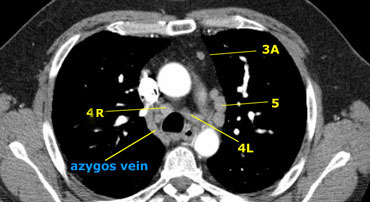

Hình ảnh ở mức trên của thân động mạch phổi cho thấy hạch cạnh dưới khí quản bên phải và bên trái. Cũng có hạch nhóm 3 và nhóm 5.

Hình ảnh ở ngang mức thấp của khí quản, trên góc carina.

Hạch nhóm 4L, nằm giữa thân động mạch phổi và động mạch chủ nhưng không thuộc cửa sổ phế chủ do chúng nằm ở giữa của dây chằng động mạch.

Hạch ở phía bên của thân động mạch phổi thuộc nhóm 5.

4R. Cạnh dưới phải khí quản (Lower Paratracheal)

Từ chỗ giao nhau của tĩnh mạch vô danh (tĩnh mạch cánh tay đầu trái) với khí quản đến bờ dưới của tĩnh mạch Azygos.

4L. Cạnh dưới trái khí quản (Lower Paratracheal)

Từ bờ trên quai động mạch chủ đến bờ trên động mạch phổi trái.

5. Hạch ở dưới quai động mạch chủ (Subaortic)

Hạch từ dưới quai động mạch chủ đến nhánh đầu tiên của động mạch phổi trái.

5. Dưới quai động mạch chủ

6. Cạnh động mạch chủ